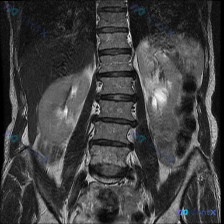

整理到一份腹部MRI冠状位T2加权图像的资料,附带提了一句“脊柱侧弯”,但实际看下来核心发现完全在肾脏上。 先把影像里的关键信息列一下: - 肝脏、脾脏、右肾看起来还好; - 左肾基本被一个大范围的病变占了,正常皮髓质结构不清,边缘也不太规则; - T2信号很杂,有明显的极高信号区(可能是液体、坏死...

整理到一份影像讨论资料,有点意思—— 最初的问题直接指向「脊柱侧弯(Scoliosis)」,但拿到手的T2加权冠状位MRI主要切的是双肾区域,没直接显示脊柱序列。 先看目前给出的肾脏影像描述: - 右肾:位置、轮廓、集合系统基本正常 - 左肾:形态改变,集合系统+部分肾实质弥漫性不均匀T2高信号,部...

病例分享与分析 基本病例信息 - 患者:42岁女性 - 既往史:多发性硬化症,反复尿路感染病史 - 主诉:腰部疼痛伴发热,急诊就诊 - 体征:体温38.8℃,左侧肋椎角压痛 - 诊疗经过:收入院后予静脉万古霉素治疗,3天后症状无改善,尿培养提示粪肠球菌生长 --- 分析思路整理 看到这个病例,第一反...